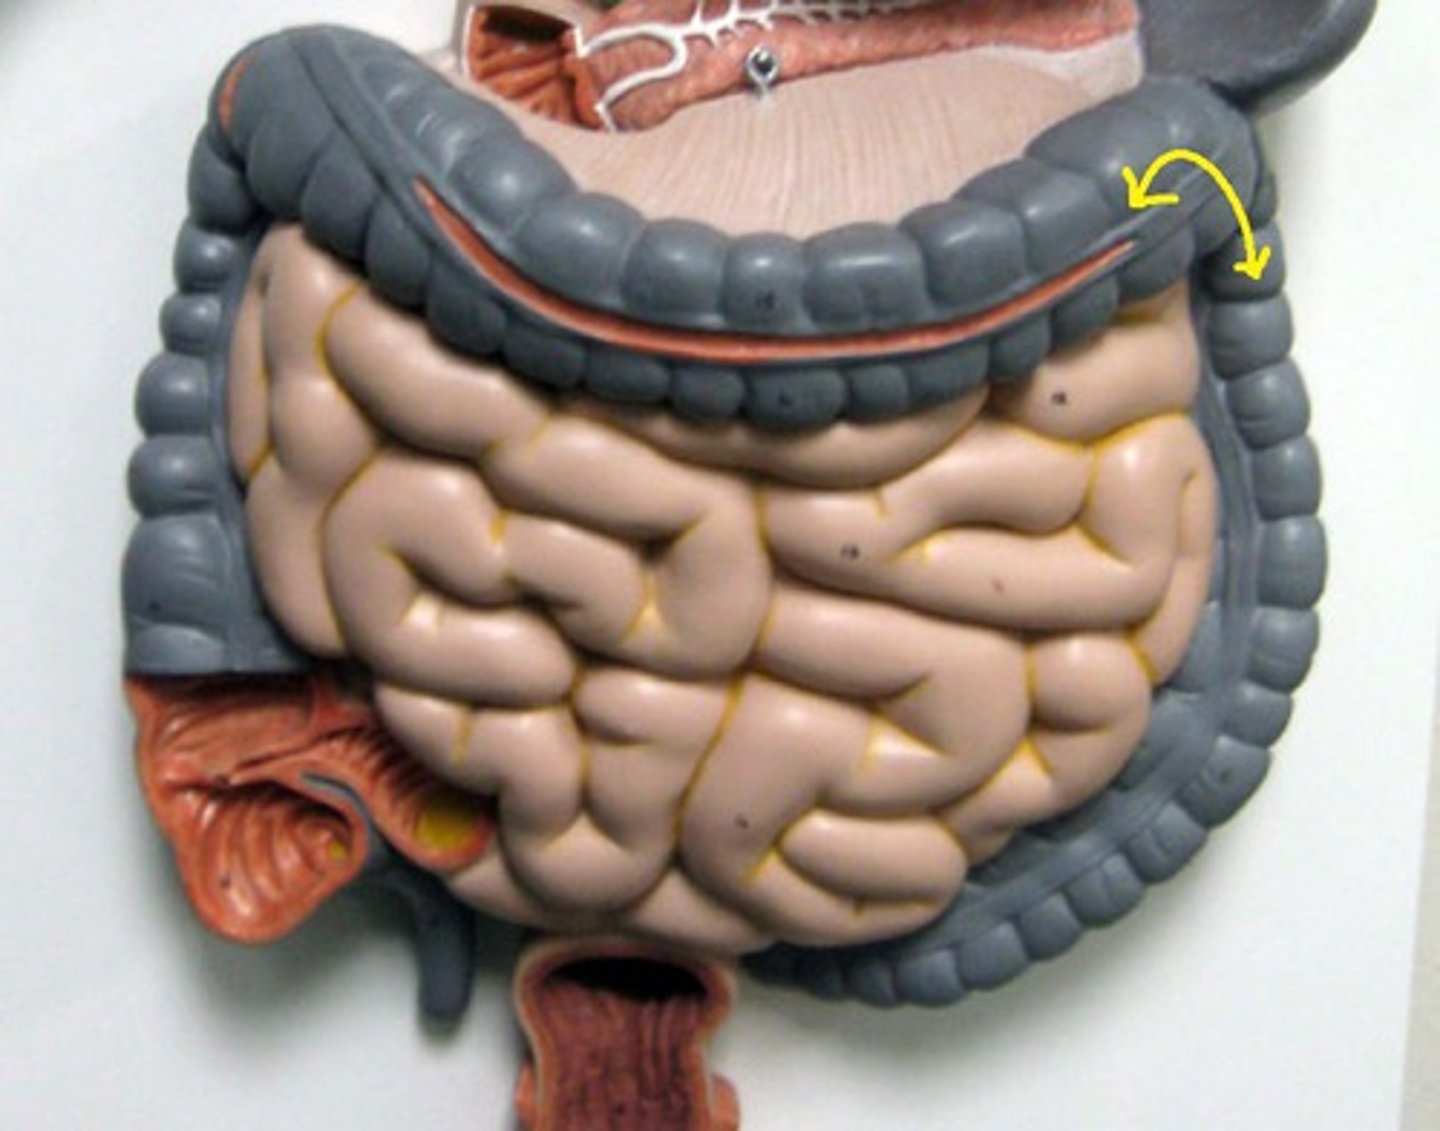

large intestine

cecum

Specific

cecum

ascending colon

Specific

transverse colon

Specific

descending colon

Specific

sigmoid colon

specific

illeocecal valve

Apendix

haustrum / haustra

taeniae coli

rectum

E

hepatic flexure

splenic flexure